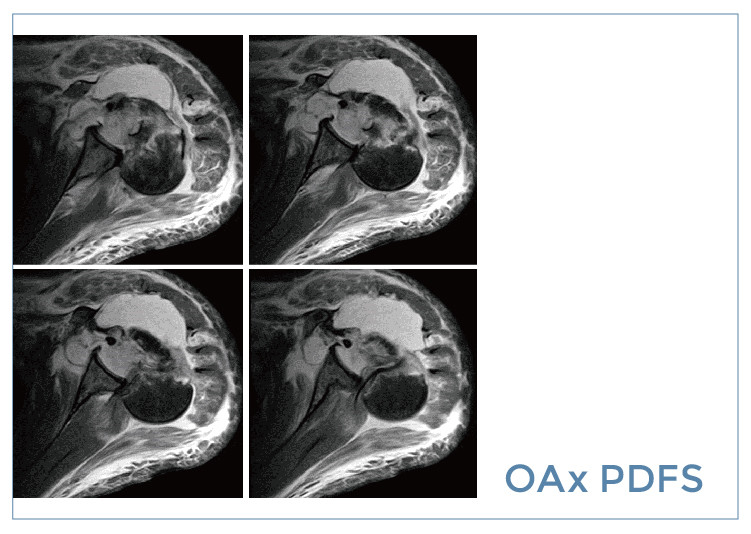

【朗润影像档案】20190906磁共振影像病例结果讨论